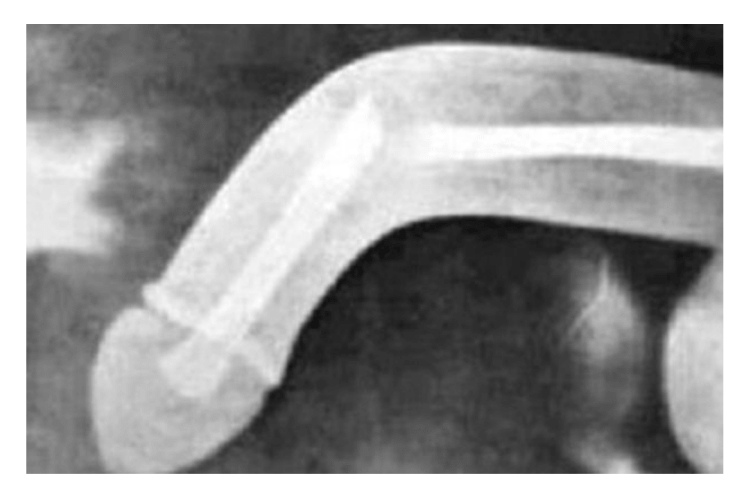

Gãy dương vật thực chất là gãy bao xơ, máu tràn ra ngoài bao, gây ứ máu, sưng tấy dữ dội. Gãy dương vật xảy ra khi dương vật cương cứng bị một lực ngang hay lực theo trục tác động mạnh giống như một chấn thương kín, gây ra tăng đột ngột áp lực nội thể hang, vượt quá sức căng của bao trắng, làm bao này rách.

- Dương vật sưng to nhưng mềm, bầm tím.

- Vết bầm do máu tụ có thể lan đến vùng mu, xuống bìu và tầng sinh môn.

Khi bị "gãy kiếm" các quý ông hãy gạt bỏ những ngại ngùng, khẩn trương tới bác sĩ để được điều trị khẩn cấp. Trong trường hợp gãy nhẹ, tổn thương không quá nhiều, các bác sĩ lấy máu tụ, khâu vá lại chỗ rách (thường ở mặt bên thể hang, ngược với hướng bẻ và nằm gần gốc dương vật).

Phẫu thuật này khá đơn giản và sau khi khâu vá, dương vật sẽ trở lại bình thường, không có vấn đề gì về việc tiểu tiện hay ảnh hưởng gì đến chuyện con cái sau này. Bác sĩ sẽ rạch da phía dưới rãnh qui đầu hoặc rạch tại vị trí tụ máu dọc theo thân dương vật. Máu tụ được lấy bỏ, làm sạch, các vết rách được khâu lại bằng chỉ tan chậm. Sau 1 – 2 tuần thì các vết rách có thể ổn định như cũ.